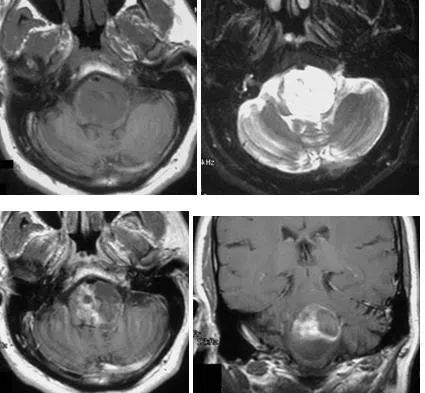

1、脑干毛细胞型星形细胞瘤:儿童患者较常见的神经胶质肿瘤,也是较常见累及小脑的肿瘤。值得一提的是该肿瘤有良性的生物行为,10年生存率达94%,大部分发生于20岁以前患者。小脑、视神经、视交叉及下丘脑是较常见的发病部位,但是该肿瘤也可发生于大脑半球、脑室及脑干。MRI通常表现为囊性肿块伴壁结节强化,有时候也表现为实性肿块无瘤周水肿,在脑干,其通常累及中脑及延髓,而浸润型胶质瘤通常累及脑桥。

(横断位T1WI示一低信号肿块累及脑桥延髓交界区,T2WI及FLAIR呈高信号;横断位、冠状位、矢状位T1WI C示片状、不规则形强化)

(矢状位及横断位T1WI示中脑及脑桥上部见一囊性肿块伴壁结节)